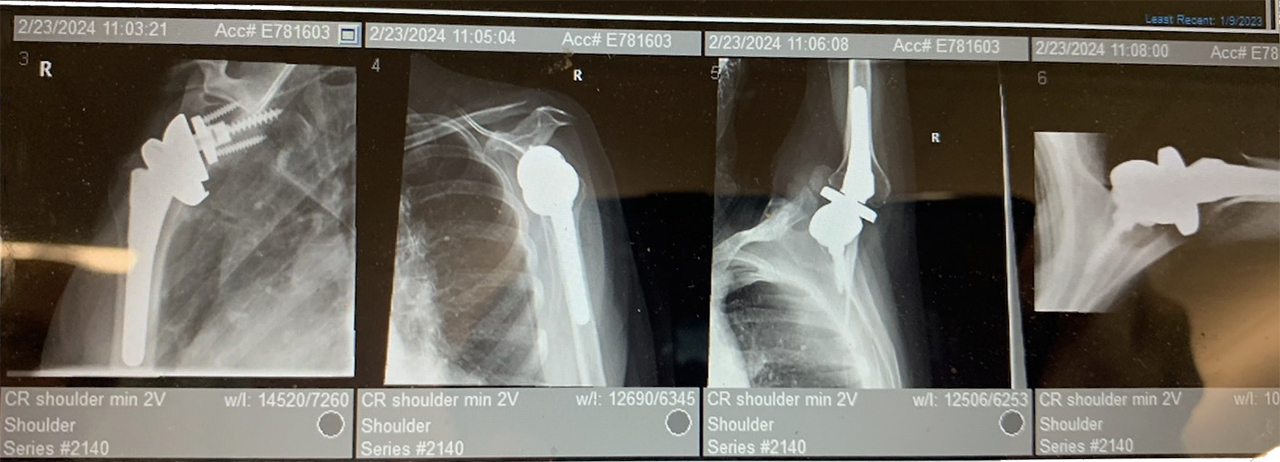

On November 30, 2023, Mary underwent her first surgery, performed by Dr. Jason Silva at Ortho Carolina, on her right shoulder.

With recovery going well, she had her 3-month follow-up x-ray. The x-ray technician ignored Mary 3 times when her range of motion was at its limit. They continued to move her arm higher and higher. This caused an immediate onset of pain.

On December 23, 2024, she was required to have revision surgery. Loose parts in her right shoulder were found and were replaced by another surgeon at another hospital.